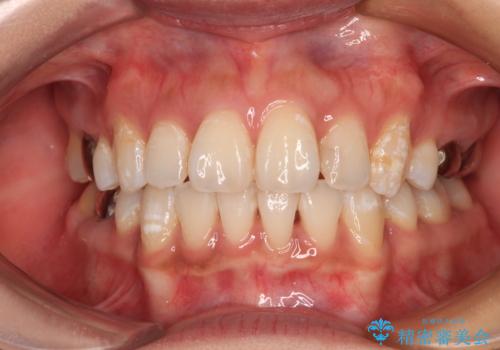

- 八重歯と叢生を気にして来院された患者様です。

上下の前歯が非接触であり、叢生や八重歯が顕著であったため、上顎左右第一小臼歯2本を抜歯して排列することとしました。

抜歯により移動量が多くなるため、ワイヤーや補助装置を活用し、その後インビザラインによる矯正治療を行うこととしました。